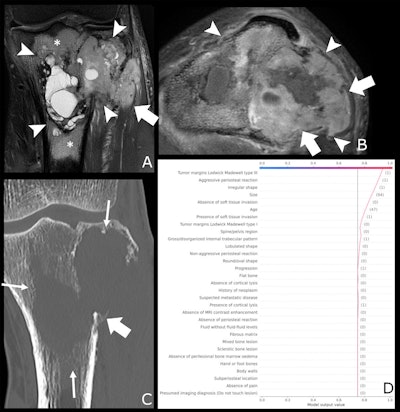

A 47-year-old male patient with knee pain for 10 months. (A) Coronal T2-weighted fat-saturated and (B) axial T1-weighted fat-saturated post-gadolinium MRI scans show a lytic lesion of the proximal tibia with an irregular shape (arrowheads), soft tissue invasion (fat arrow in A), and perilesional bone marrow edema (*). (C) Coronal CT image reconstructed with bone kernels of the same lesion show permeative margins (arrows) and a discontinuous periosteal reaction (fat arrow). (D) Shapley additive explanations decision function graph shows the impact of lesion characteristics on the ensemble classifier’s prediction. After a one-hot encoding for categorical features, present features are represented as "(1)" and absent features as "(0)," whereas continuous features are represented by the actual measurement. The estimated malignancy probability of this lesion was 0.94, which corresponds to Bone Tumor Imaging Reporting and Data System grade V. This lesion corresponded to an undifferentiated sarcoma at histologic examination and was graded as aggressive by the human reader.Radiology

A 47-year-old male patient with knee pain for 10 months. (A) Coronal T2-weighted fat-saturated and (B) axial T1-weighted fat-saturated post-gadolinium MRI scans show a lytic lesion of the proximal tibia with an irregular shape (arrowheads), soft tissue invasion (fat arrow in A), and perilesional bone marrow edema (*). (C) Coronal CT image reconstructed with bone kernels of the same lesion show permeative margins (arrows) and a discontinuous periosteal reaction (fat arrow). (D) Shapley additive explanations decision function graph shows the impact of lesion characteristics on the ensemble classifier’s prediction. After a one-hot encoding for categorical features, present features are represented as "(1)" and absent features as "(0)," whereas continuous features are represented by the actual measurement. The estimated malignancy probability of this lesion was 0.94, which corresponds to Bone Tumor Imaging Reporting and Data System grade V. This lesion corresponded to an undifferentiated sarcoma at histologic examination and was graded as aggressive by the human reader.Radiology